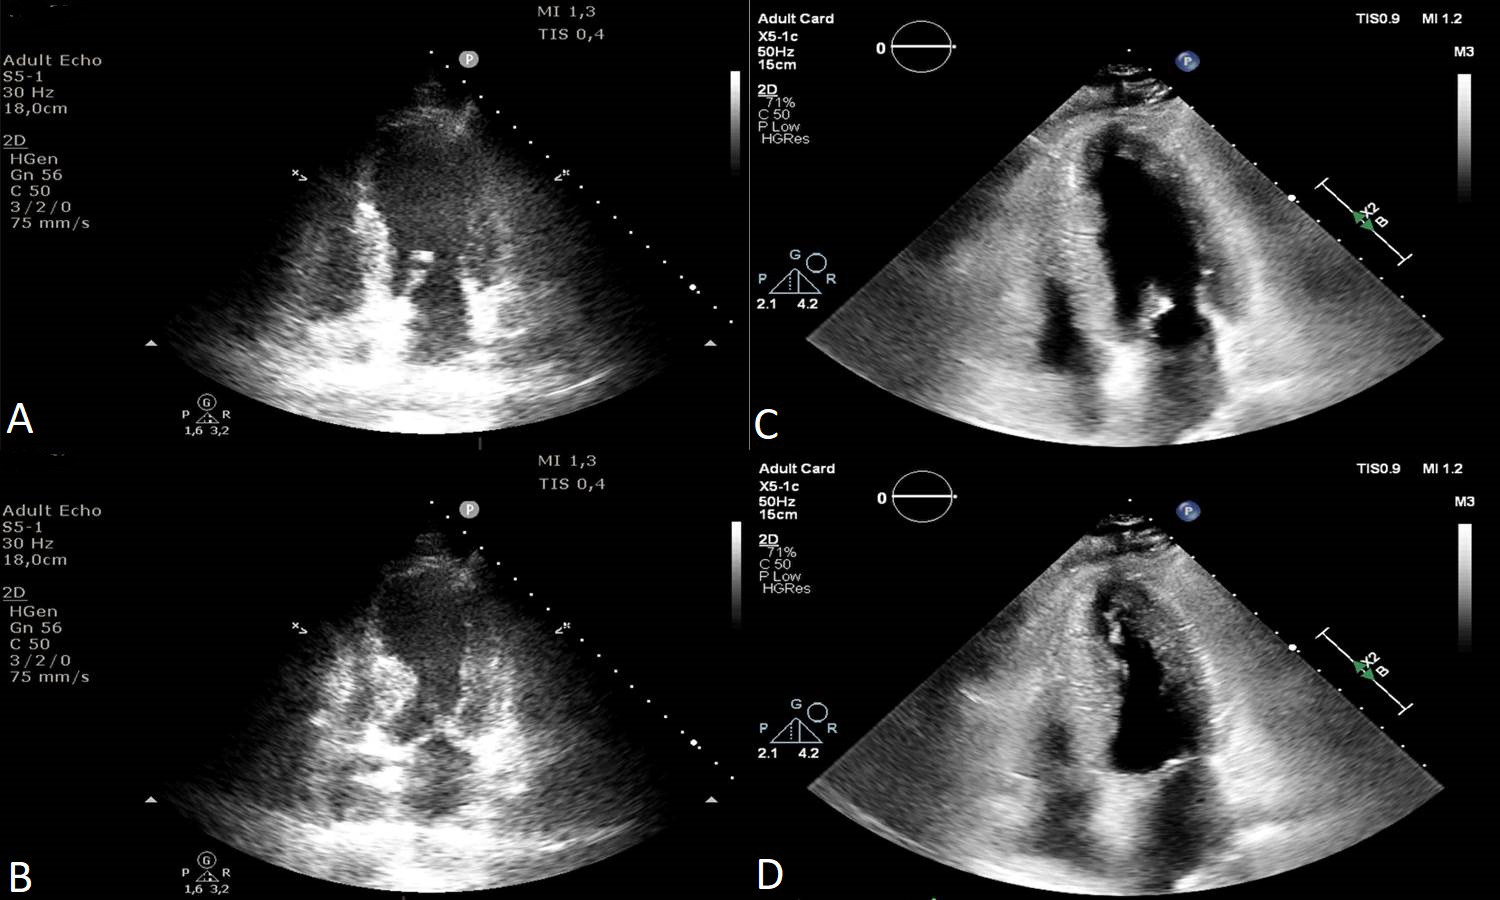

Alongside the LV systolic function, LV diastolic function needs to be evaluated in the acute phase and then at follow-up. Kumar et al. [81] revealed that LVEF improved alongside diastolic function: E value, E/A ratio and e’ values improved over time (Fig. 3). Both lower LVEF and higher E/e’ ratio were associated with in-hospital complications in TS patients [37, 54].

Fig. 3.Transthoracic echocardiography images apical four-chambers views of a 73 year-old female patient with Takotsubo Syndrome showing the evolution of diastolic function. E wave velocity progressed from 40 cm/s in the acute phase to 70 cm/s at one month follow-up, the E/A ratio from 0.5 to 0.8 (A and B). Lateral e’ velocity increased from 4 cm/s to 8 cm/s and E/e’ ratio from 10 to 8.7 (C and D). 2D, two dimensional; PW, pulsed wave doppler; TDI, tissue doppler imaging.